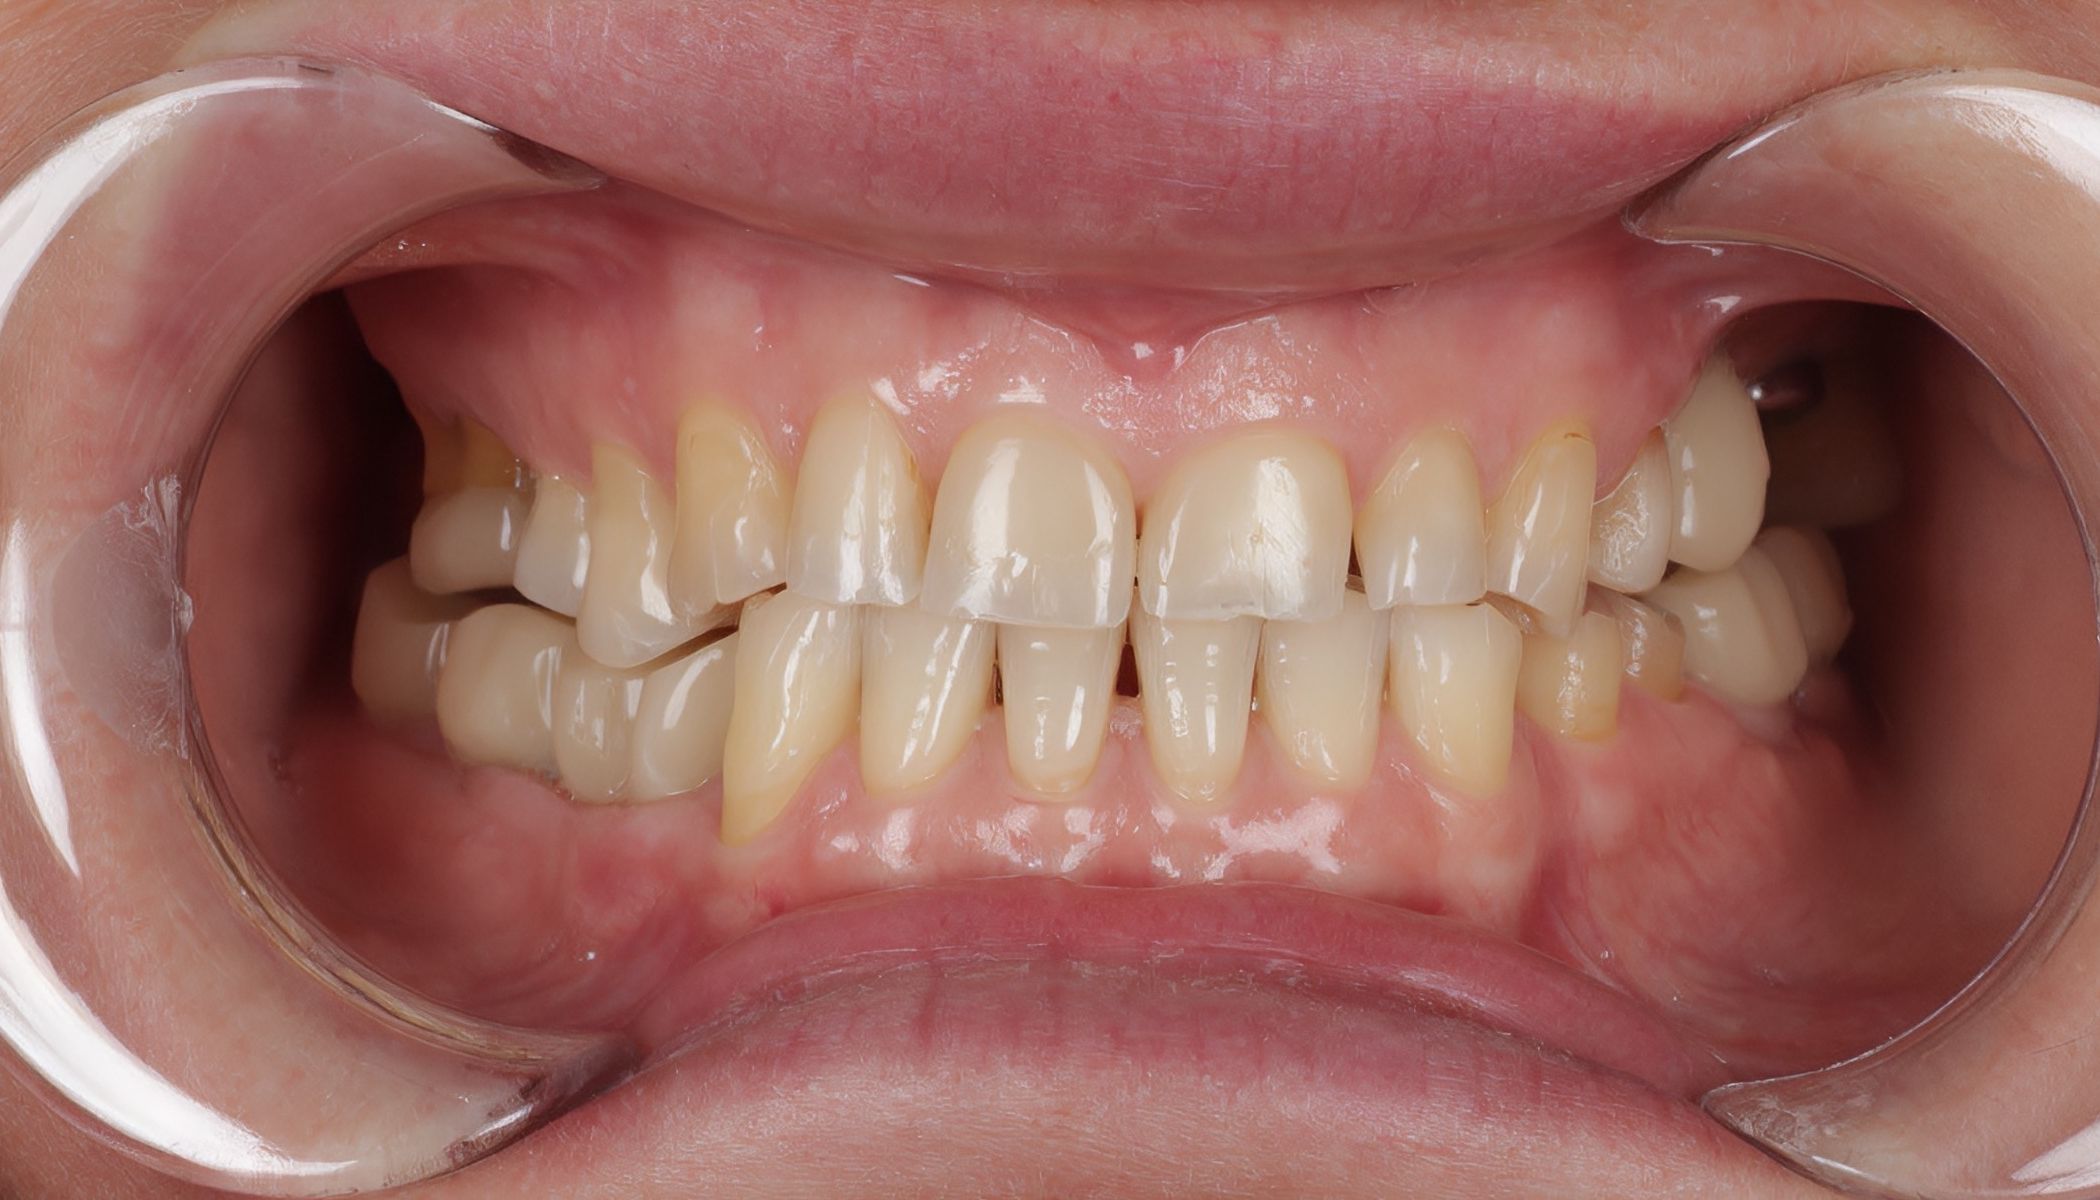

Пациентка обратилась с жалобами на отсутствие жевательных зубов на верхней челюсти слева. Также её беспокоило изменение формы и размеров оставшихся зубов. Лечение было проведено комплексно и поэтапно.

На первом, хирургическом этапе были удалены несостоятельные зубы и установлены имплантаты. Затем изготовлены временные коронки с опорой на установленные импланты. Через три месяца после имплантации зубов был проведён второй этап — диагностическое моделирование. В рамках этого этапа мы смоделировали будущую улыбку пациентки и изготовили временные реставрации на все зубы верхней и нижней челюстей.